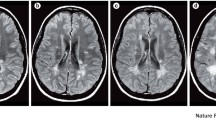

Several different methods are currently available to evaluate cervical spinal cord atrophy in patients with MS, including the measurement of the cross-sectional area at several anatomical levels or measurment of the volume between two levels (Fig. 2) [107, 108].

Example of spinal cord volume measurement on a three-dimensional (3D) T1-weighted image from a patient with progressive multiple sclerosis (PMS) (Jim, ver. 6). a Using the inferior border of C5 as a reference, a marker was placed at this level and then, moving back from C5, a marker was set every 10 slices until the first marker at C2 was reached (b), with the final output with the outlined cord shown

Although several technical difficulties hamper the reliability of cerebellar volume measurement, a number of automated and semi-automated image analysis methods have been developed and implemented in recent years (Fig. 3). In one study, cerebellar GM volume was found to be reduced in SP-MS patients compared to healthy controls [123]. In another study, atrophy of specific cerebellar lobules in PMS patients correlated with clinical disability, as assessed by means of 9-hole-peg-test and cognitive tests [124].

Reproduced from Cocozza et al. [124]

Example of cerebellar segmentation on a 3D T1-weighted image from a patient with PMS. Middle image: the isolated cerebellar grey matter obtained by SUIT (spatially unbiased infratentorial toolbox), shown in red, is superimposed to the T1-weighted image. Right image: the SUIT cerebellar atlas aligned in the native subject space.